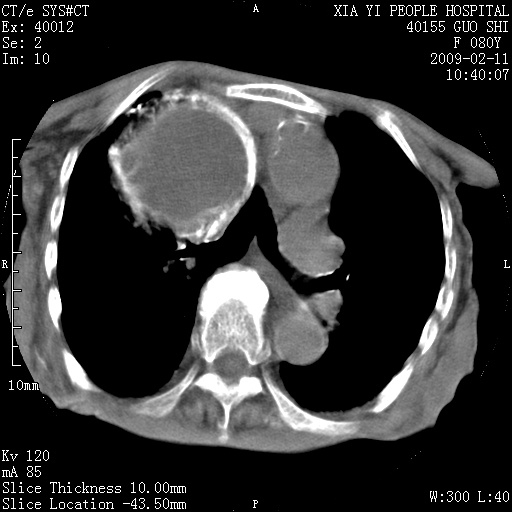

以下是引用随光逐影在2009-2-16 16:34:00的发言:[br]1)考虑右前纵隔皮样囊肿。2)双侧少量胸腔积液。

以下是引用zjzjr在2009-2-16 17:30:00的发言:[br]支持囊性畸胎瘤 双侧少量胸腔积液。